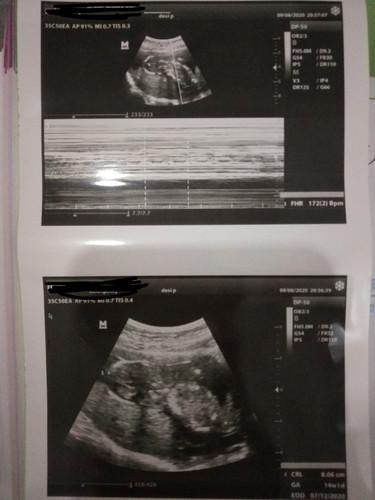

Asaalamualikum bunda ...mohon maaf sebelumnya bunda baru hamil pertama, saya baru usg cuman perbedaannya jauh dari bidan 19w4d tapi pas usg baru 14w1d ,,,apa dokter ngukur dari panjang bayi ya ,,tadi juga gak sempat banyak tanya ke dokternya,,klo baca dari hasil usg saya blm terlalu paham boleh sharing bunda yang sudah pengalaman?